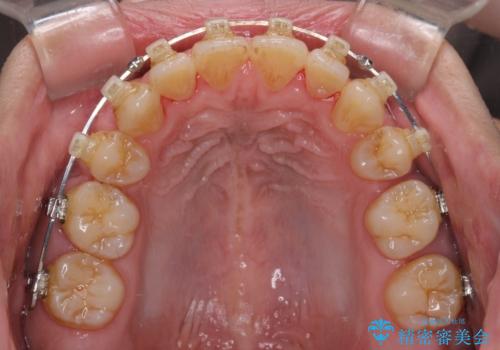

- クリアブラケット

舌の突出癖を改善するためのトレーニングを指導していましたが、なかなか改善することができず、ワイヤー装置を外してからも上下前歯に隙間ができやすい状況でした。